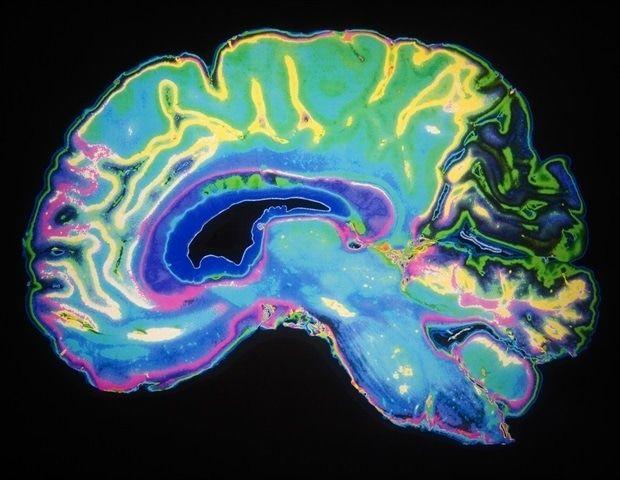

WashU MedicineJun 23 2025 A new AI-based technology that rapidly maps the brain to locate sensitive areas that control speech, vision, movement and other critical functions has received authorization from the Food and Drug Administration (FDA), enabling it to be marketed to hospitals with the aim of enhancing the precision of neurosurgeries. The technology was developed by researchers and clinicians at Washington University School of Medicine in St. Louis to more precisely guide neurosurgeons in performing delicate brain surgeries to remove tumors or treat epilepsy, for example. The Cirrus Resting State fMRI Software is being brought to market by Sora Neuroscience, Inc., a WashU startup company that licensed the technology from the university. The technology is built on decades of WashU Medicine leadership in the field of neuroscience and functional imaging of the brain. Its development has been funded by the National Institutes of Health (NIH), with the support of private investors. "This is going to be a sea change for clinical imaging and brain mapping," said Eric C. Leuthardt, MD, the Shi H. Huang Professor of Neurological Surgery, who developed the technology at WashU Medicine and co-founded Sora Neuroscience. "Now clinicians have access to a broader and more accessible way to look at brain function that can quickly provide insights across neurosurgery applications and for brain diseases, which will benefit patients." The development of Cirrus software highlights the vital role academic entrepreneurs and startup companies play in translating discoveries into real-world solutions that improve people's lives, said Doug E. Frantz, PhD, vice chancellor for innovation and commercialization at WashU. Transforming years of scientific advances into a tool that surgeons can use in the operating room is only possible through partnerships with commercial ventures like Sora Neuroscience and the WashU Medicine faculty who helped launch the company. This is a clear example of how entrepreneurship drives the translation of groundbreaking research from the lab to patient care." Doug E. Frantz, PhD, vice chancellor for innovation and commercialization, WashU The Cirrus Resting State fMRI software can identify distinct networks of brain activity that govern key activities such as language, vision and movement, and create maps of their locations. Typically, such maps require specialized staff and up to an hour in a scanner to map such networks. The algorithms in the Cirrus software, which are based on artificial intelligence technology, can analyze patterns of linked activity in a resting brain that are known to correspond to specific brain functions. They can complete their mapping of multiple brain networks from as few as 12 minutes of functional magnetic resonance imaging (fMRI), which tracks changes in the brain's blood flow to identify areas of neurological activity. The scans for the Cirrus software are performed while a person is at rest in the MRI machine, as opposed to performing a task such as speaking or moving fingers and toes to activate specific brain networks. Leuthardt explained that task-based fMRI is only able to create usable maps for surgeons approximately two-thirds of the time, typically due to patient movement or inability to participate in the task. In contrast, 87% of Cirrus' scans can be reliably incorporated into a surgeon's operating plan. Task-based fMRI is also limited to those who can perform these tasks and follow instructions. For that reason, Cirrus Resting State fMRI software procedure will make fMRI mapping available to a much larger group of patients, said Joshua Shimony, MD, PhD, a professor of radiology at WashU Medicine Mallinckrodt Institute of Radiology, who was a co-investigator with Leuthardt on the studies underlying the technology and is also a scientific advisor to Sora Neuroscience. "Resting state fMRI can be done on patients who have difficulty with task-based fMRIs, such as children, patients who are confused or who need sedation or anesthesia, or those who are hard of hearing or don't speak English," he said. Leuthardt said that while the technology was initially developed in his laboratory, the underlying data drew from decades of WashU Medicine-led research on resting-state fMRI imaging. Carl Hacker, MD, PhD, who recently completed his WashU neurosurgery residency training, developed the AI-based algorithms driving the Cirrus program while he was a doctoral student in Leuthardt's laboratory. Physicians and scientists have collaborated for years to develop and advance the imaging analytic capability for pre-surgical brain mapping and conduct studies on its effectiveness. WashU's Office of Technology Management filed the initial patents more than a decade ago and licensed the technology in 2021 to Sora Neuroscience. The company was founded in 2020 by Leuthardt along with Hacker and WashU Medicine professor of radiology Daniel Marcus, PhD, and assistant professor of radiology Mikhail Milchenko, PhD. WashU Medicine